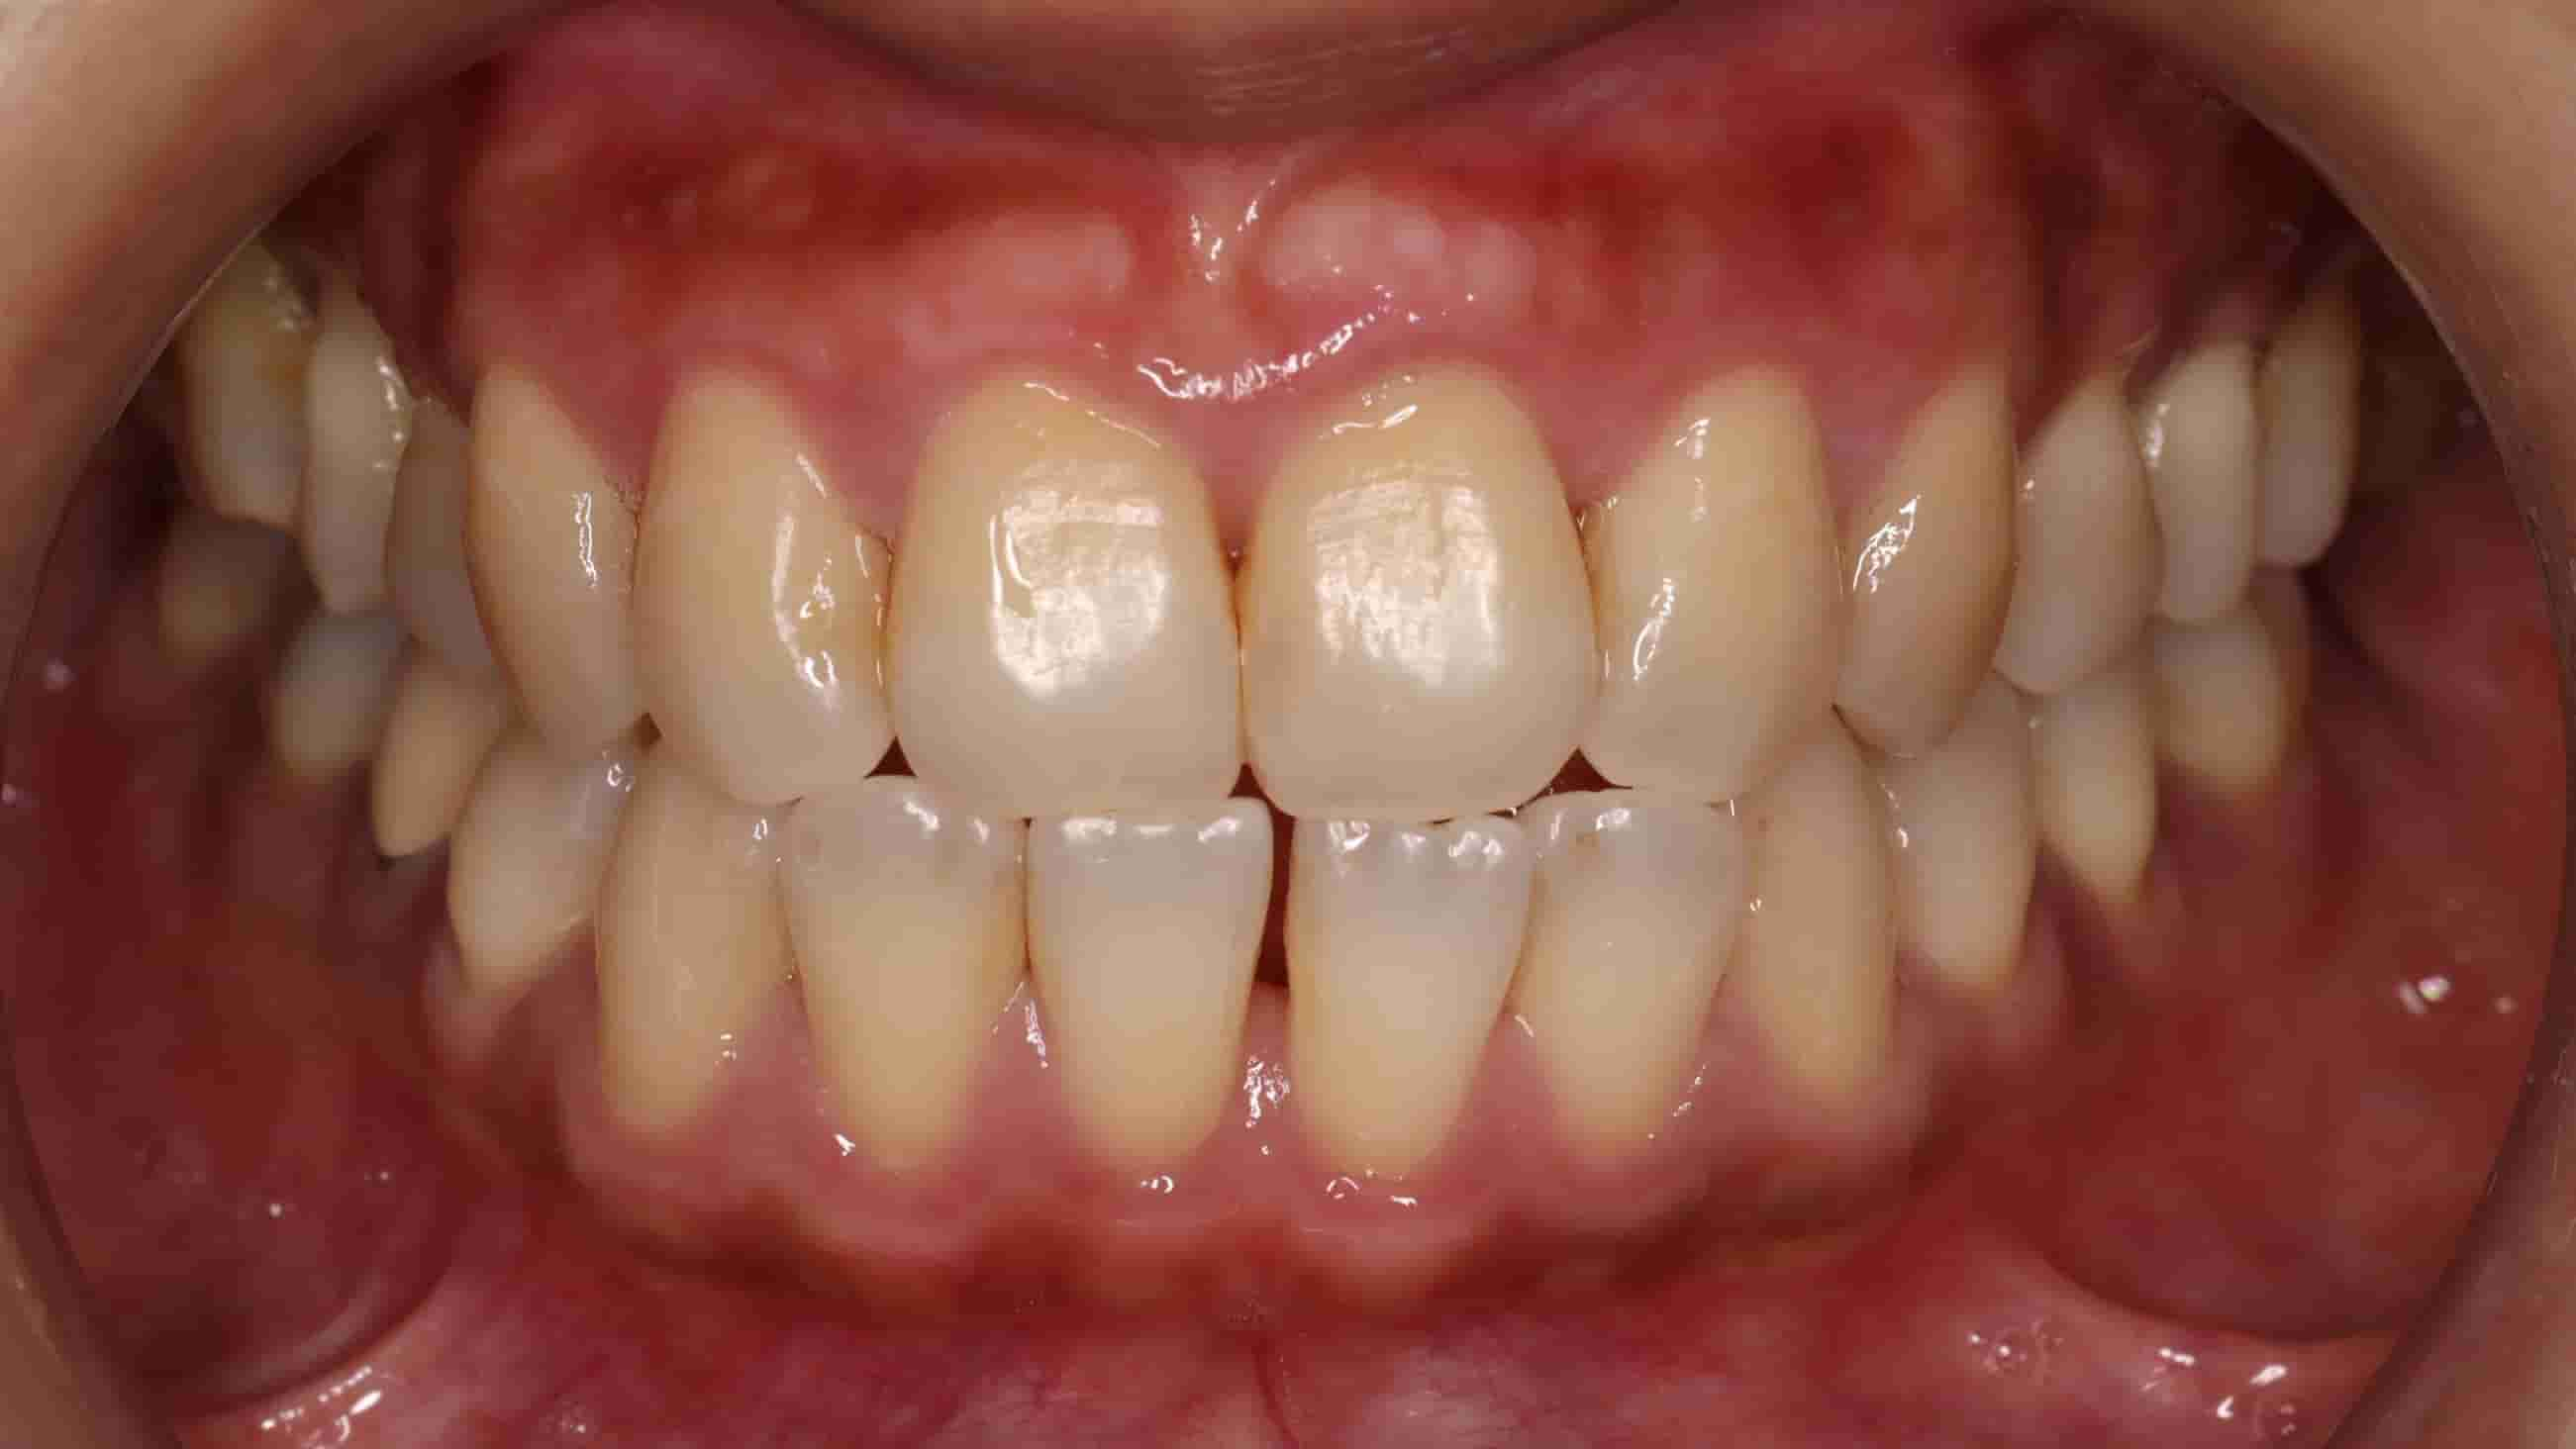

古小姐第一次來到診間時,主要是希望能做全口的詳細評估與檢查,因為她進食較黏稠的食物,牙齒容易感到疼痛,刷牙的時候容易出血,更令她困擾的問題是,她以前因為蛀牙拔掉牙齒,但沒有進行後續處理,左下方有缺牙的情況,除了導致牙齒開始出現縫隙,長期習慣用右邊進食,也讓她兩邊咬合都不太舒服。

咬合與牙縫問題 - 影響整體美觀與功能

第三階段:重建牙齒正常排列&空間

等到牙齦狀況穩定後,開始約一年的隱適美療程。矯正過程不只是要關閉牙縫,更重要的是要調整牙齒的角度和位置。由於缺牙時間過久,導致上方對咬牙失去抗衡,隨時間逐漸往下掉,因此也需要藉由矯正的力量把它們推回正確的位置。